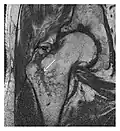

Proximal femoral fractures usually occur in osteoporotic patients, and their signs include subtle neck angulation, trabecular angulation, and subcapital impaction line. A frog-leg lateral view may be helpful if the greater trochanter is short enough. However, positioning can be difficult because of hip pain. In patients with strong suspicion of proximal femoral fracture and negative radiographs, MRI limited to coronal T1 W images and scintigraphy can be highly valuable (Figures 13 and 14). Such an option, with limited examination time, is cost-effective and allows reliable exclusion or confirmation of the diagnosis, preventing an unnecessary stay at the hospital or delayed treatment. Moreover, MRI helps to detect soft tissue abnormalities which are more frequently seen in femoral, acetabular, and pubic injuries than sacral lesions. Concomitant fractures are also frequently seen in typical pelvic sites.[1]

Figure 13: Partial osseous avulsion of the gluteal muscles at the greater trochanter in a 59-year-old man who presented with the right hip pain without a history of trauma. Lauenstein view and anteroposterior and radiographs (not shown) did not show an obvious fracture line or disruption of bony contours in the acetabulum or the right femoral neck. (a) Coronal T1-weighted MRI displays an incomplete fracture line extending partially from the greater trochanter (arrow). (b) Coronal short tau inversion recovery MRI shows heterogeneous hyperintensity in the same region (arrow) as well as hyperintensity within the gluteus medius and minimus muscles (arrowheads) consistent with tissue edema and hematoma.[1]